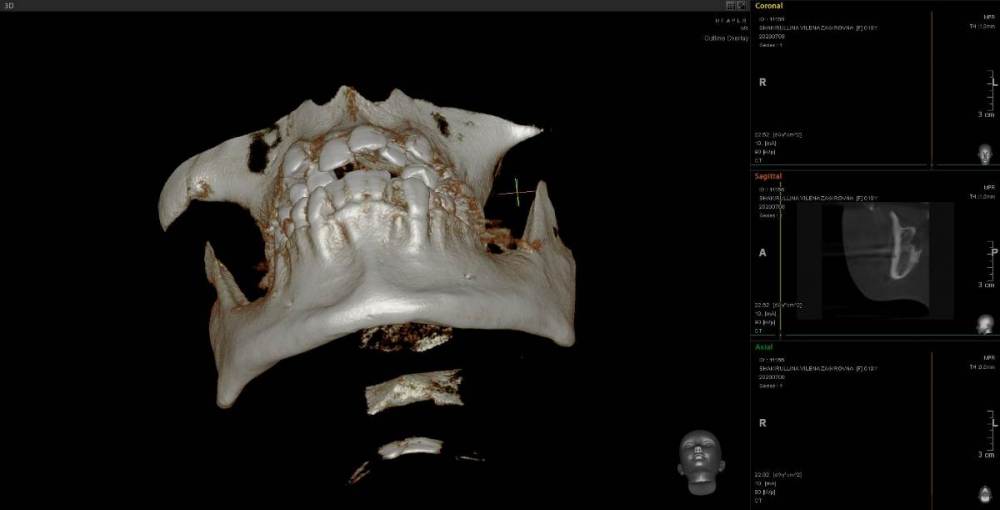

Женька Опубликовано 23 июня, 2021 Поделиться Опубликовано 23 июня, 2021 Коллеги, приветствую. Пришла пациентка с направлением на удаление 1.6-2.6 по ортодонтическим показаниям. Расспросив узнал, что принял решение такое ортодонт, тк премоляры интактны, а вот 1.6 эндодонтически пролечен. 2.6 с пломбой. Вопрос, оправдан ли такой подход? Есть лишь реконструкция КТ. Зубы я конечно не удалил, тк о таком подходе слышу впервые. Связавшись с ортодонтом узнал, что нестандартное удаление... Что думаете? p/s мудрые почему-то пока не удаляем... Ссылка на комментарий